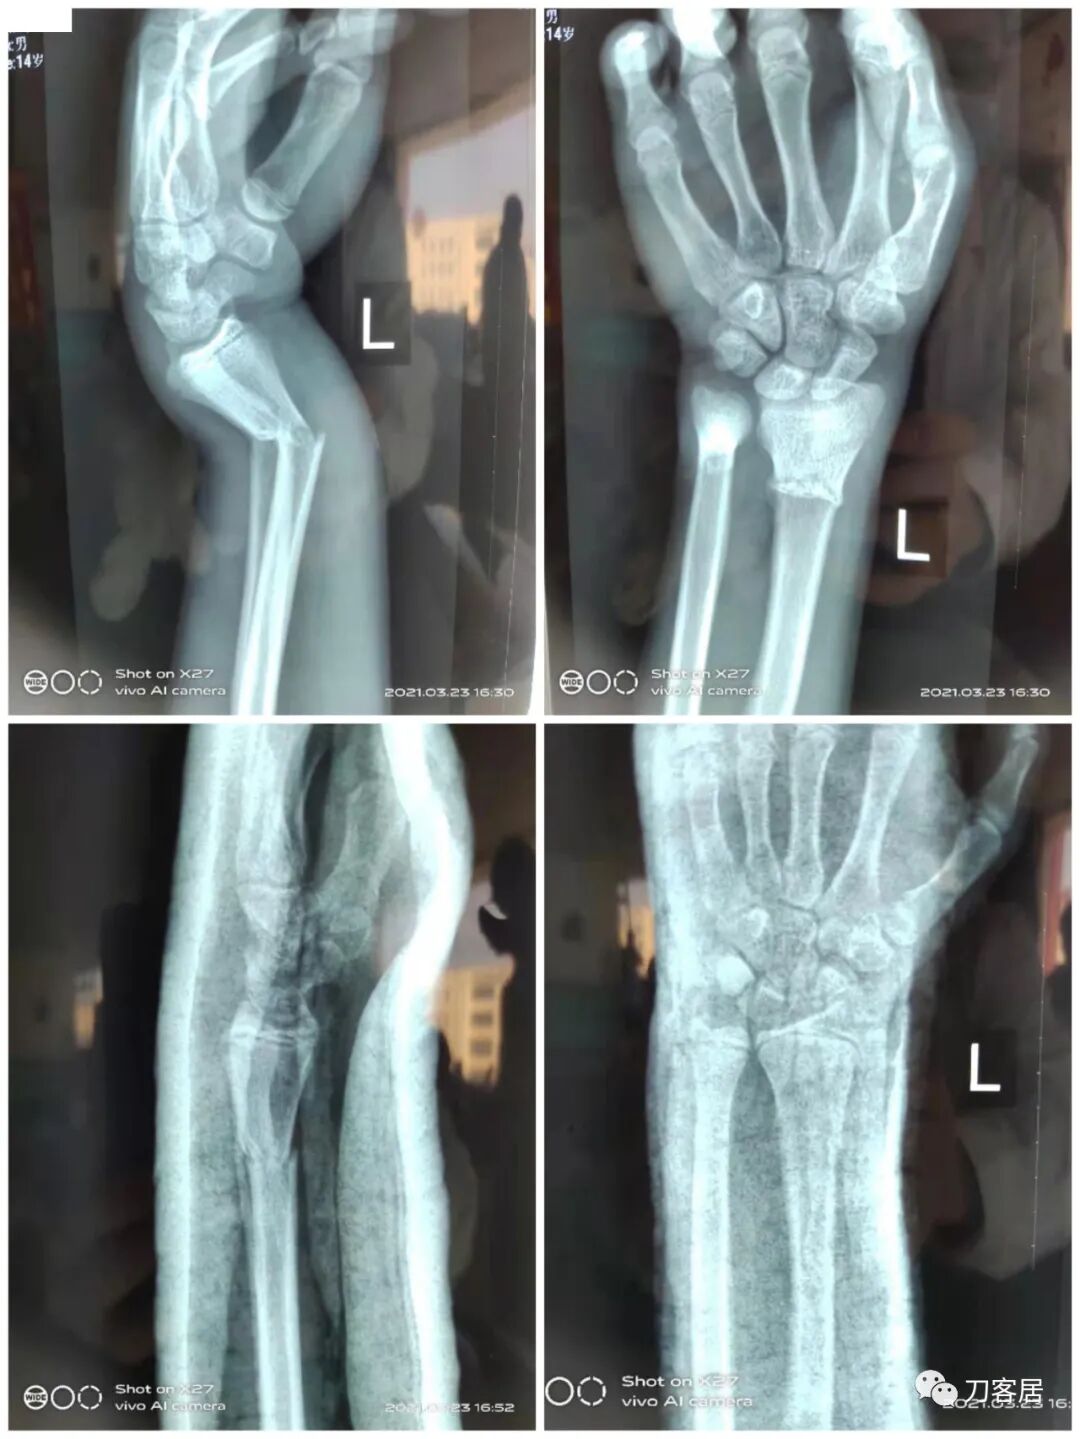

下面是这个6岁孩子,尺桡骨远端双骨折的术前及术后片子和外观照片。

1.  这是一个很简单的6岁儿童无移位的尺桡骨远端骨折。没有皮肤损伤,没有移位,没有骨折碎块儿。

2.  这个骨折处理起来也很简单,单纯的打石膏托或者中医的小夹板,或者正规的包括腕关节和肘关节的管型石膏外固定4周即可治愈该骨折。实在不行,如果这个孩子比较听话,不太调皮的话,用一本书,一个三角巾悬吊固定4周,都可以治愈该骨折。但是给这个患者用外固定架做了手术,而且桡骨远端的几颗克氏针距离骨折线太近,其中一枚克氏针进入到骨折间隙内。从这个术中图片来看,术者的外固定手术技术也有待于进一步的提高。毕竟术者应该还很年轻。从X线片来看,前臂及手的尺侧有不透光影,应该还使用了外固定石膏绷带托,而且我猜测应该是高分子的石膏绷带托,这个是纯属猜测,不一定是对的,不过如何解释前臂尺侧的不透光影呢?如果真是用了石膏绷带外固定的话,那为啥要做手术呢?外固定架术后就不该再用石膏绷带托辅助了。